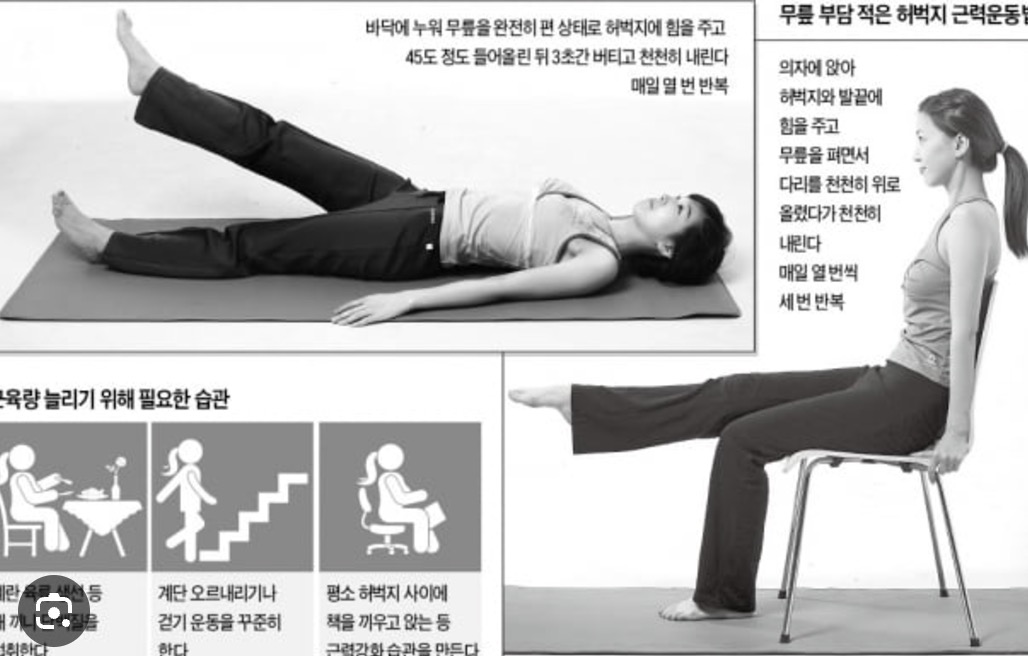

3. 실내에서 할 수 있는 관절 운동

추운 겨울철에도 실내에서 안전하게 할 수 있는 관절 운동을 소개합니다:

- 앉았다 일어나기 운동 (하루 10회씩 3세트)

- 다리 들어올리기 (각 다리 15초씩 유지)

- 무릎 굽혔다 펴기 (20회씩 3세트)

- 발목 돌리기 운동 (각 방향 10회씩)